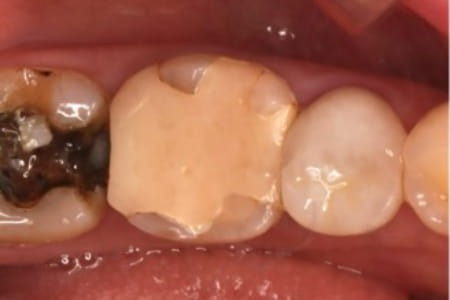

近所のかかりつけの歯科医院で、「再治療できないから奥歯を抜くしかない」と言われた。

あきらめきれず、HPで探して当院へ来院。

外すと中がドロドロに虫歯に感染していました。